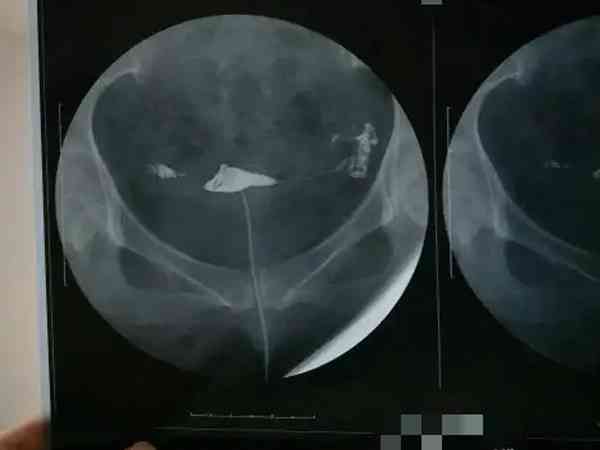

输卵管造影经X线的子宫输卵管造影是通过导管向宫腔及输卵管注入造影剂,利用X线诊断仪行X线透视及摄片,根据造影剂在输卵管及盆腔内的显影情况来了解输卵管是否通畅、阻塞部位及宫腔形态的一种检查方法,很多人听说它是一项手术都认为其过程很麻烦,但其实输卵管造影流程还是很简单的。输卵管造影手术过程是什么输卵管造影是临床上应用较为广泛的方法之一。经X线的子宫输卵管造影是通过导管向宫腔及输卵管注入造影剂,利用X线...

输卵管造影是要用X线观察造影剂的流动情况,从而判断是否存在堵塞或者其他情况,这种检查输卵管是否存在问题的准确率非常高,基本上已经达到了98%左右,所以检查后发现问题最好及时治疗,如果是常规的输卵管堵塞可能会存在不孕的情况,但若是因为盆腔炎所导致的输卵管堵塞的话,患者还会出现腹痛、分泌物增多等情况,可以自行判断。输卵管造影中文名输卵管造影术适应证不孕症、子宫肿瘤等检查时间月经后3-7天就诊科室妇科检...